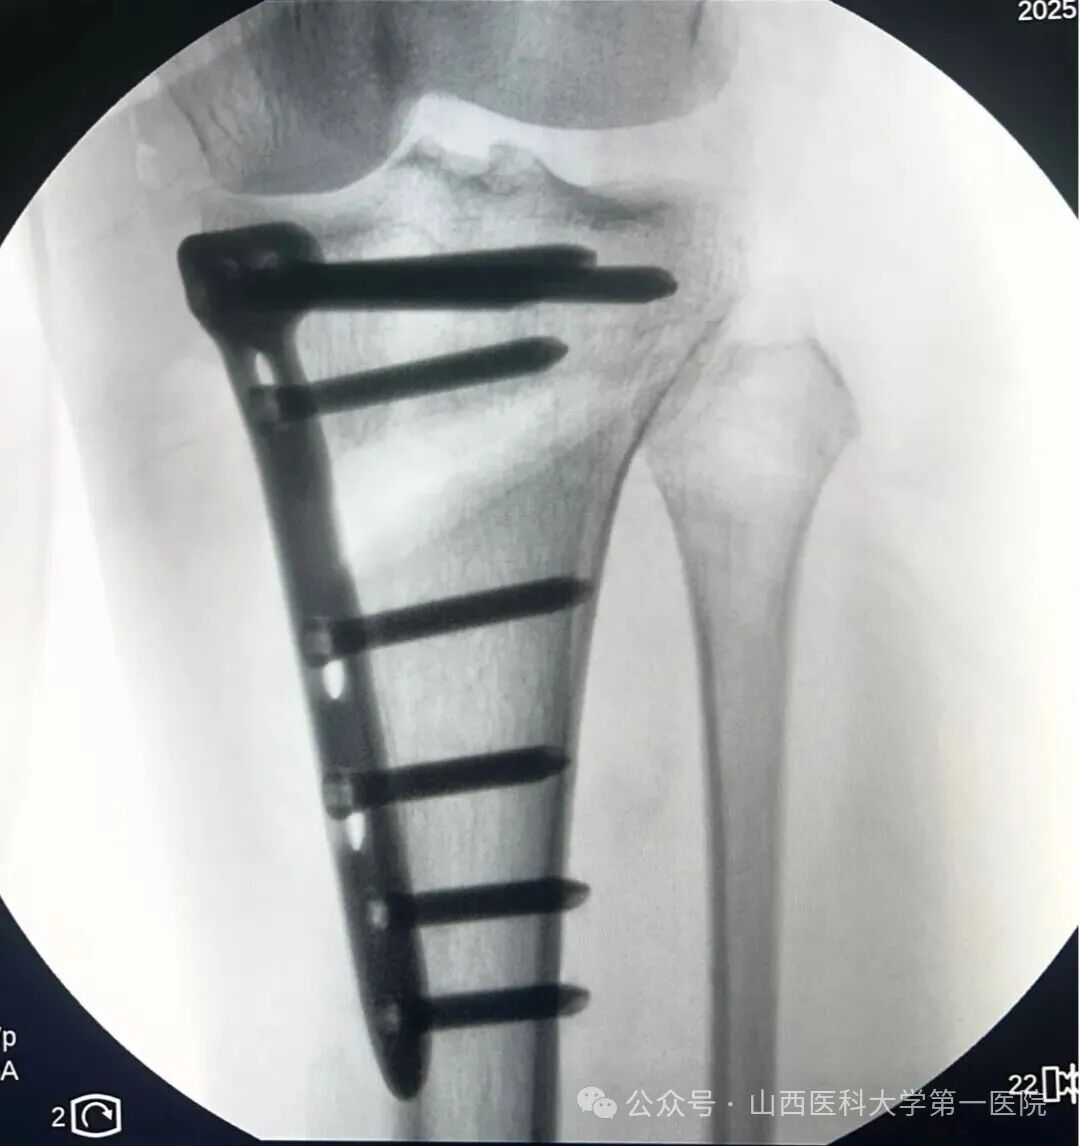

术中通过3D-PSI导板进行截骨

放置钢板后行X线确认位置满意